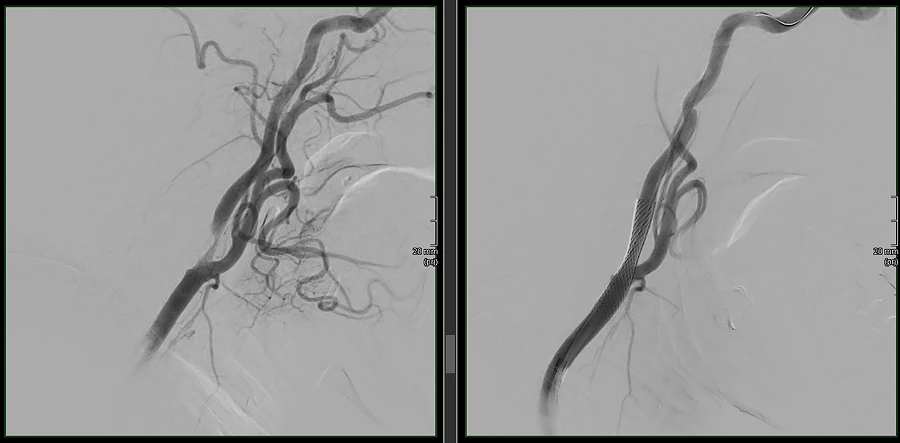

Patient:innen mit asymptomatischer oder symptomatischer Karotis-Stenose, denen eine Operation empfohlen wird, haben damit einen Anspruch auf eine ärztliche Zweitmeinung – zulasten der gesetzlichen Krankenversicherung. Der Zweitmeinungsanspruch gilt insbesondere vor einer geplanten operativen Revaskularisation (TEA), nicht jedoch zwingend vor einem interventionellen Eingriff (CAS). Dennoch ist die Entscheidung aus Sicht der Interventionellen Radiologie hochrelevant.

Die DeGIR begrüßt die Aufnahme der Karotisstenose-Behandlung in die Zweitmeinungsrichtlinie ausdrücklich. Denn sie schafft die Möglichkeit, Patient:innen umfassender über alternative Therapieverfahren – einschließlich der minimal-invasiven Karotis-Stentangioplastie – aufzuklären. Interventionelle Radiolog:innen sollten sich aktiv als Zweitmeinungsgebende positionieren und ihre besondere Expertise in der Risiko-Nutzen-Abwägung minimal-invasiver Verfahren in interdisziplinäre Entscheidungsprozesse einbringen.